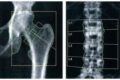

Dexa femorale e lombare

LINEE GUIDA PER L’ESECUZIONE IN CONVENZIONE DELLA DENSITOMETRIA OSSEA FEMORALE E LOMBARE CON TECNICA DI ASSORBIMENTO RAGGI X (REGIONE SICILIA) Un controllo successivo è consigliabile solo dopo un intervallo di 18 mesi, in presenza di precedente referto patologico con T-score…